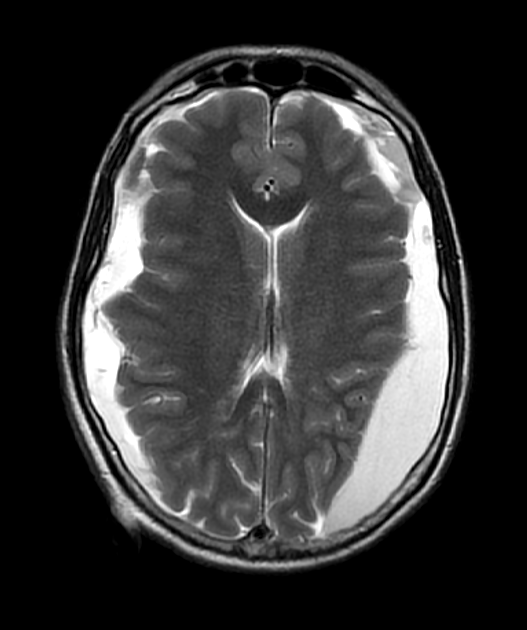

- MRI findings:

- T1: hypointense (isointense to CSF)

- T2: hyperintense (isointense to CSF)

- FLAIR: suppressed signal (unlike subdural haematoma)

- DWI: no restricted diffusion

- No enhancement on post-contrast images

- A 70-year-old patient with gait disturbance and cognitive impairment underwent an intraventricular shunt for normal pressure hydrocephalus (albeit without classical imaging appearances).

- The patient had a persistent headache post-operatively. On the third post-operative day, an MRI showed bilateral subdural collections containing small regions of susceptibility (due to blood product) that resulted in effacement of the lateral ventricles.